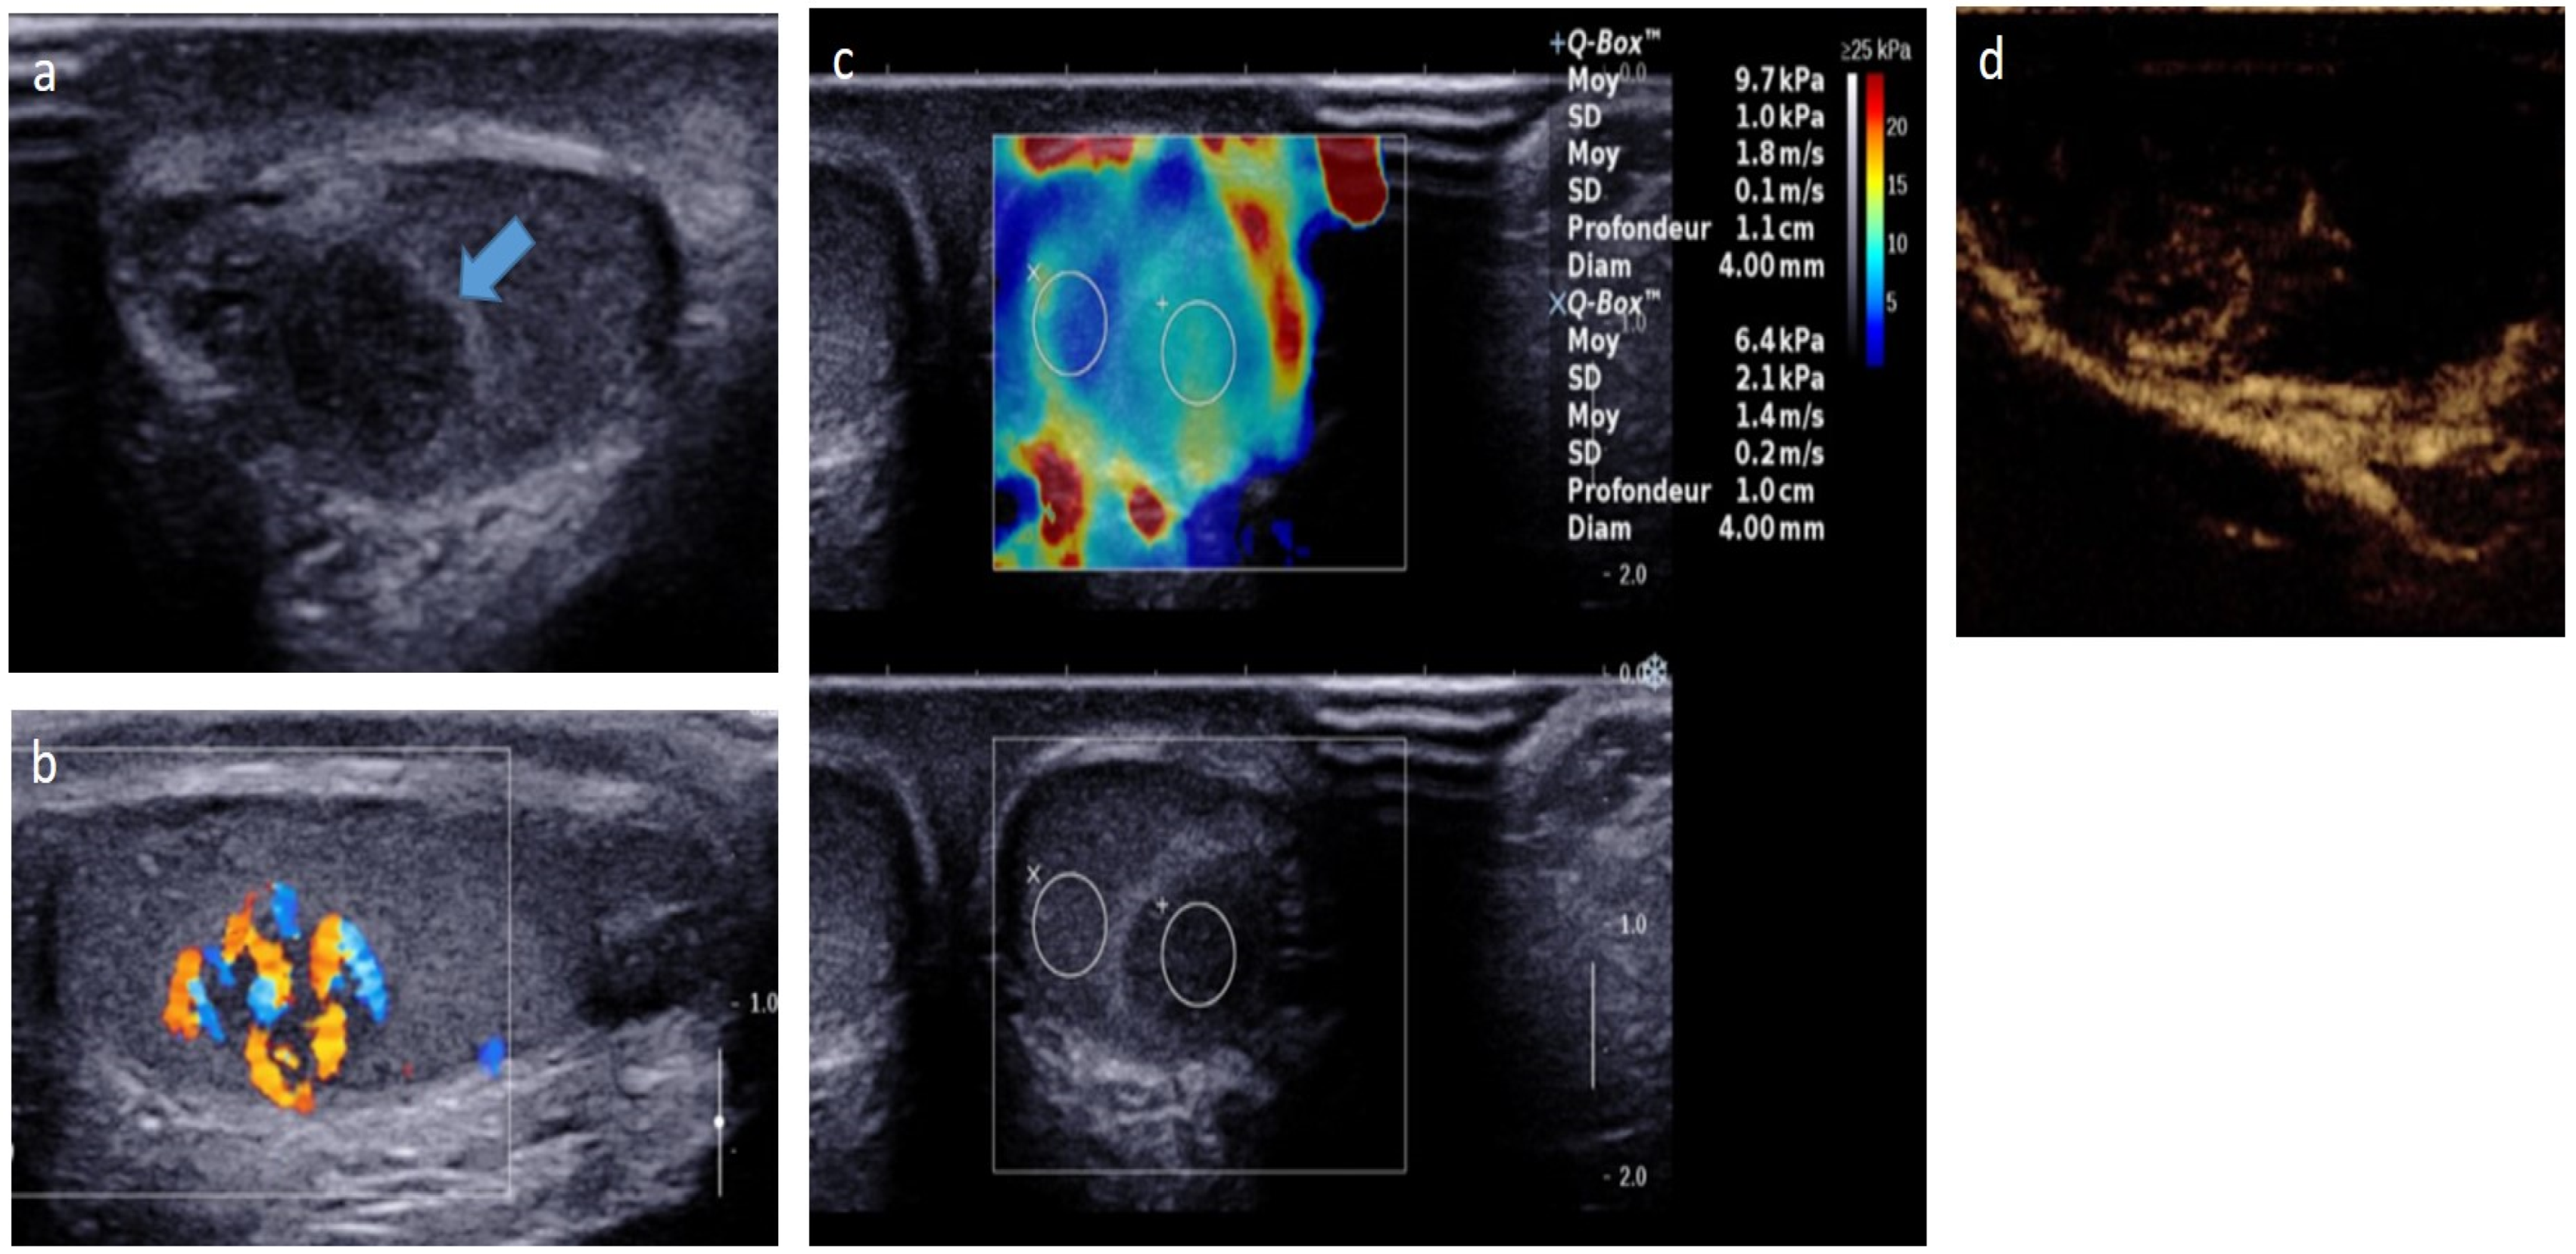

4.5.1. Leydig Cell Tumors (LCTs)

- Grand, T.; Hermann, A.-L.; Gérard, M.; Arama, E.; Ouerd, L.; Garrouche, N.; Rocher, L. Precocious puberty related to Leydig cell testicular tumor: The diagnostic imaging keys. Eur. J. Med. Res. 2022, 27, 67. [Google Scholar] [CrossRef]

- Di, M.; Qin, J. Role of contrast-enhanced ultrasound with Sonazoid in management of small testicular Leydig cell tumours: A case report with literature review. Andrologia 2021, 53, e14078. [Google Scholar] [CrossRef]

- Manganaro, L.; Vinci, V.; Pozza, C.; Saldari, M.; Gianfrilli, D.; Pofi, R.; Bernardo, S.; Cantisani, V.; Lenzi, A.; Scialpi, M.; et al. A prospective study on contrast-enhanced magnetic resonance imaging of testicular lesions: Distinctive features of Leydig cell tumours. Eur. Radiol. 2015, 25, 3586–3595. [Google Scholar] [CrossRef]

- Drudi, F.M.; Valentino, M.; Bertolotto, M.; Malpassini, F.; Maghella, F.; Cantisani, V.; Liberatore, M.; De Felice, C.; D’Ambrosio, F. CEUS Time Intensity Curves in the Differentiation Between Leydig Cell Carcinoma and Seminoma: A Multicenter Study. Ultraschall Med. Eur. J. Ultrasound 2015, 37, 201–205. [Google Scholar] [CrossRef] [PubMed]

- Maxwell, F.; Izard, V.; Ferlicot, S.; Rachas, A.; Correas, J.-M.; Benoit, G.; Bellin, M.-F.; Rocher, L. Colour Doppler and ultrasound characteristics of testicular Leydig cell tumours. Br. J. Radiol. 2016, 89, 20160089. [Google Scholar] [CrossRef] [PubMed]